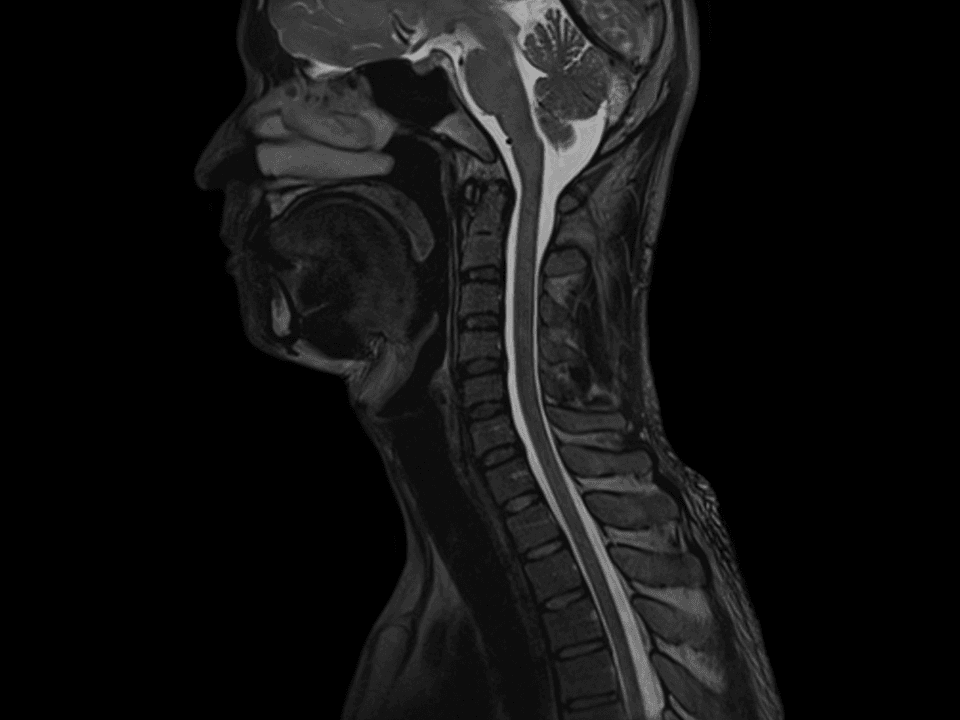

Easy patient setup and state-of-the-art imaging performance for C-Spine, T-Spine, L-Spine, and Whole Spine.